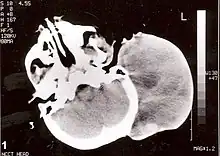

Non-contrast CT scan of head showing a large mass without any intracranial extension. The diagnosis was post-auricular congenital alveolar rhabdomyosarcoma.